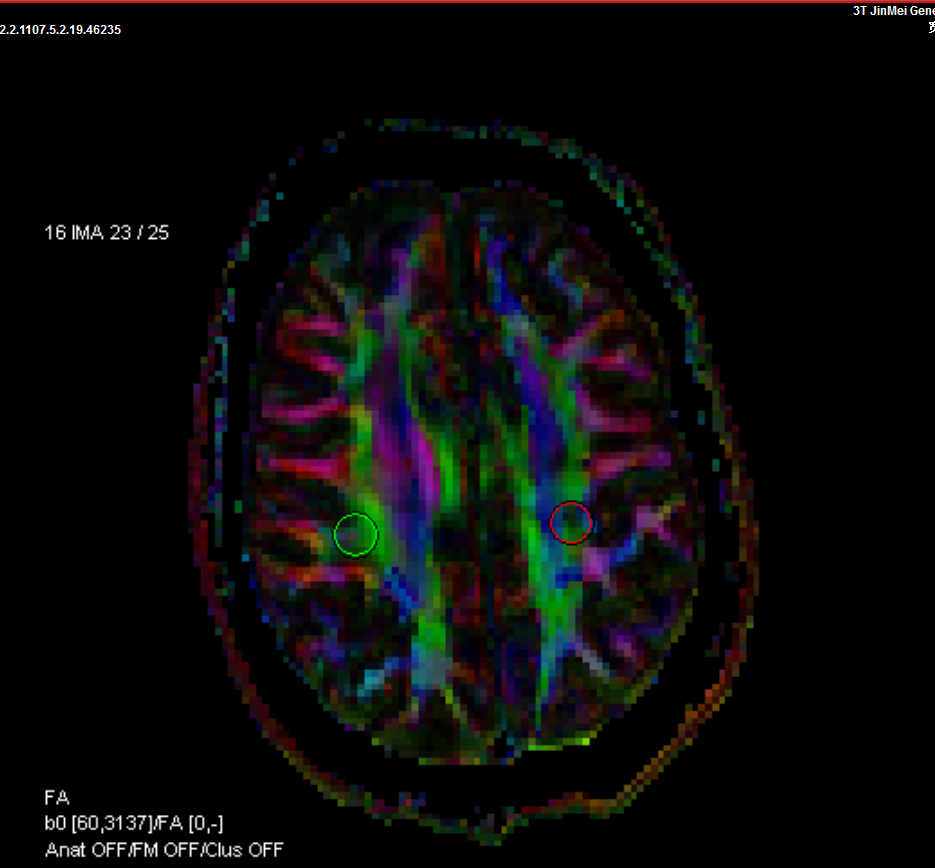

擴(kuò)散張量成像DTI

1、PTSD是一種反應(yīng)性障礙,是精神創(chuàng)傷后高發(fā)、嚴(yán)重的精神疾病,通過(guò)多模態(tài)功能磁共振成像技術(shù)可了解瓦斯爆炸后PTSD患者腦結(jié)構(gòu)和腦功能的改變,為PTSD的診療提供客觀依據(jù)。